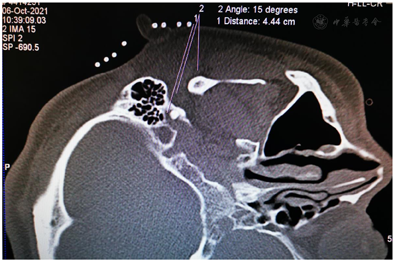

鉴于MS与HFS的临床表现有高度相似之处,我们设想,用于治疗HFS的面神经射频技术有望用治疗MS。经报请医院伦理委员会讨论通过(LS2019-013),决定给患者施行双侧面神经射频治疗。术前向患者及其家属详细交待操作经过和可能出现的轻度面神经麻痹并发症,取得知情同意并签署书面知情同意书后,嘱患者右侧向上侧卧于CT台上,安置血压、心电图、脉搏血氧饱和度监测设施并给予鼻导管吸氧,并在耳垂前后放置CT定位定位栅(图2)。用鼻旁窦模式拍摄头颅定位像,并对乳突区进行层厚3 mm轴位扫描,选取含茎乳孔且无颞骨鼓部骨质阻挡的CT层面作为穿刺层面,并在该层面上设计穿刺路径:以右侧茎乳孔为穿刺靶点,用CT自带测量工具软件由右茎乳孔向前上拉直线,该线与皮肤的交点即为穿刺点,测量穿刺深度(穿刺点至靶点的距离)和穿刺角度(穿刺路线与矢状面的夹角)(图3)。对穿刺点进行局部麻醉,用长度为10 cm、裸露端为5 mm的7号射频针在CT引导下穿刺至靶点(图4)并CT扫描三维重建观察确认(图5),随后用低频(2 Hz)电流进行运动神经刺激测试,0.5 mA电流电刺激即能诱发出右侧面肌出现与电刺激相同频率痉挛性抽动,见视频,给予65℃标准射频消融,同时嘱患者鼓腮、闭眼,射频第27秒鼓腮漏气,右眼不能紧闭,即停止射频,结束手术,见视频。2 d后同样于CT引导下行左侧茎乳孔穿刺面神经射频消融治疗(图6,图7,图8)。